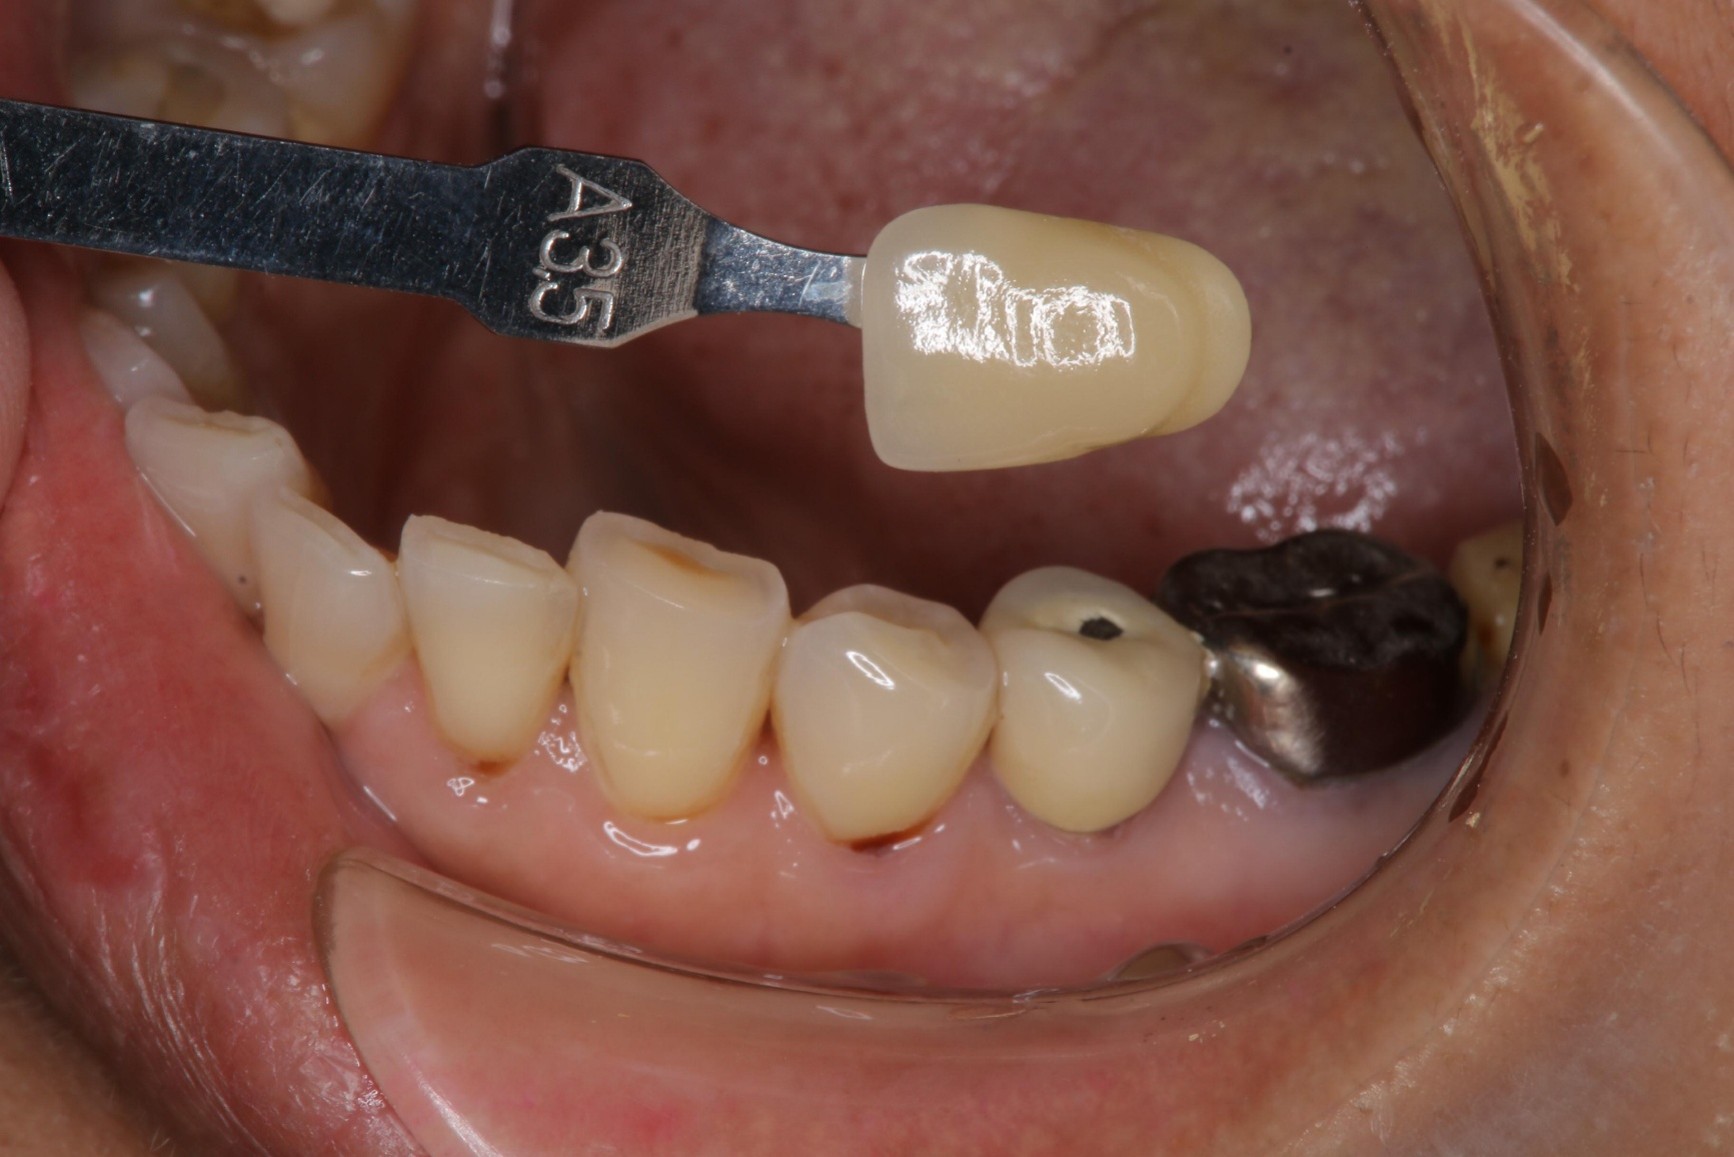

膺復前評估牙齦、牙齒狀態

照相比色